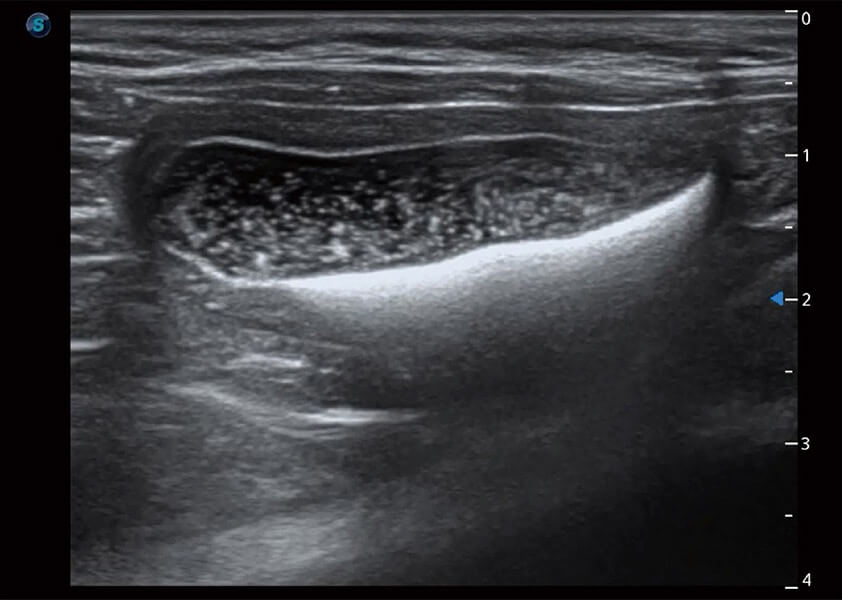

ProPet 60 作为一款高端台式动物超声设备,为动物医生的日常诊断提供了一系列贴合动物临床需求、解决临床实际问题的高级成像功能。凭借全系列高清探头,满足医生对腹部、心脏、生殖、浅表、肌骨等成像的所有需求,切实帮助您提升检查效率,提高诊断信心。

动物是人类最亲密的朋友和最值得信赖的伙伴。16877太阳集团也一直致力于探索动物专用的超声影像解决方案。 全新推出的ProPet系列,是16877太阳集团在动物超声影像智能化、专业化、精准化的一次跨越式革新。动物不能用言语来表述自己的不适,通过超声影像,ProPet系列搭建了动物医生与不同物种沟通的“桥梁”,为动物医生注入了“治愈之力”。